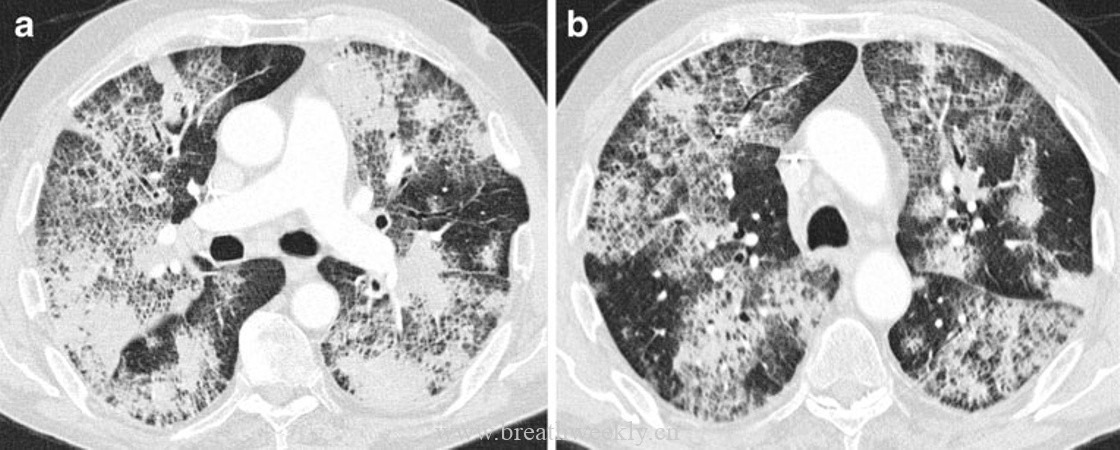

病例1:肺泡蛋白沉积症

临床资料:46岁男性,进行性呼吸困难1周,咳嗽,晨起咳白色粘痰。

影像表现:胸片显示以肺部中央为主的网状影,双肺中央密度增高。CT显示双肺斑片状铺路石征。

病理对照:肺泡内嗜酸性无定形物质,PAS染色阳性,对应表面活性物质缺乏。线状影对应腺泡边缘气腔内物质沉积(腺泡周围型)。

肺泡蛋白沉积症和外源性脂质性肺炎是气腔疾病。在肺泡蛋白沉积症中,气腔被磷脂蛋白样物质填充。CT上肺泡填充导致磨玻璃影,当邻近小叶间隔和肺泡壁的气腔被填充时,形成腺泡周围型。